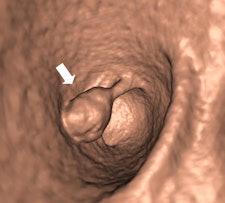

Along with his colleague Dr. Stefaan Gryspeerdt, Lefere has addressed CTC's potential pitfalls in a comprehensive paper published online January 4 in Insights into Imaging. Their top tips are to perform state-of-the-art CTC (preparation based on fecal tagging, along with colonic distension with CO2 plus injector, dual positioning, and smooth muscle relaxation), remember the general principles of interpretation, and take special care when examining the rectum and caecum.